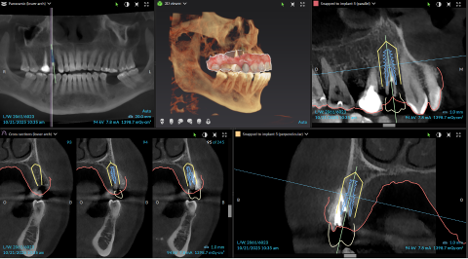

During your initial consultation at Arcadia Perio, Dr. Peterson will review your medical history, perform an oral exam, take digital X-rays, and likely consult your general dentist. Sometimes, a 3D scan is taken with our cone-beam computed tomography scanner to accurately visualize your unique anatomy and plan virtual implant treatment. The initial planning phase is as thorough as possible to optimize long-term success and determine your optimal solution.

Procedure & Same-Day Teeth

The 3D image we took during your consultation is used to create computer-aided guidance with our sophisticated X-Nav system. Visualizing the placement of your dental implants in 3D eliminates guesswork and potential complications. In the skilled hands of Dr. Peterson, proper planning combined with X-Guide Dynamic 3D Navigation during surgery elevates surgical excellence while increasing efficiency and safety. If you received full-mouth dental implants, our customized, streamlined protocol enables Dr. Peterson to fit you with temporary 3D-printed teeth within 24 hours of your surgical procedure.

Implant Treatment Planning

Clinical overview

3D planning

CBCT & planning

Planning detail

Additional planning view